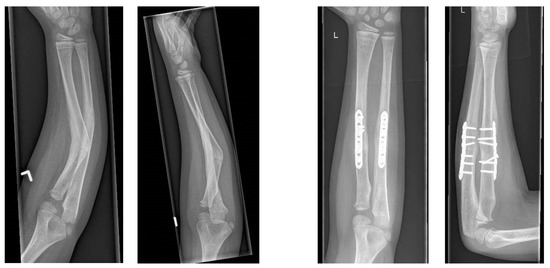

Accuracy of 3D Corrective Osteotomy for Pediatric Malunited Both-Bone Forearm Fractures

2. Materials and Methods